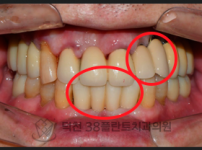

치료전후